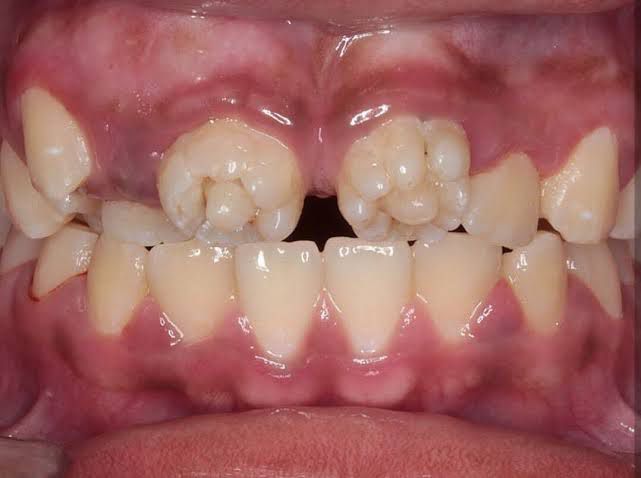

Mulberry molars are a dental condition usually associated with congenital syphilis, characterized by multiple rounded rudimentary enamel cusps on the permanent first molars.[2] Mulberry molars are physically defective permanent molars. The deformity is caused by congenital syphilis. This type of abnormality is characterized by dwarfed molars with cusps covered with globular enamel growths. These teeth are functional but can be cosmetically fixed with crowns, bridges, or implants